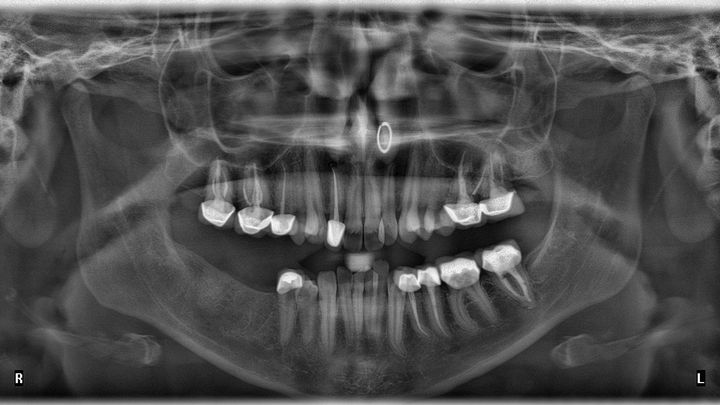

Those of you who know me know I’ve had a lot of dental procedures throughout my life. These procedures have ranged in severity—cavities turned root canals, root canals turned extractions, and so on. If you know me, you might know I am missing two molars on the right side of my bottom teeth; I haven’t chewed on that side in years. Almost all of my remaining molars have had root canals performed on them and have crowns.

To my incredible dismay, as of last month (January), I received a new diagnosis, and a new bill. I have two upper right molars that have root canals that have seemingly failed. They require what is called a retreatment—as the name aptly suggests, they re-treat the tooth, essentially performing another root canal to clean out the present infection. (This also means those glittering porcelain crowns I paid for by myself however many years ago will need to be replaced with new, equally as expensive crowns). I should note: these kinds of dental procedures, especially those in the upper region, are an urgent matter, as the infection is liable to spread if left untreated.

My current dental insurance (through UCI) is only paying out $779. The total of the procedures, after insurance, is $2,287. After including the necessary crowns (which are not covered, but rather are discounted with a contracted rate of $1,706), I am left with a grand total of $3,992.